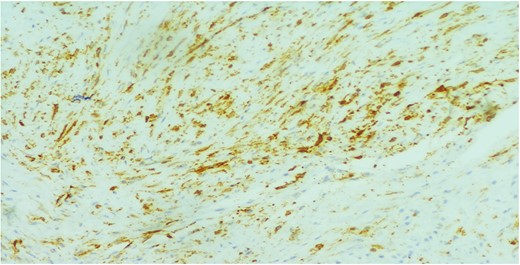

A 26-year-old female presented to our unit with recurrent right breast lump that was excised 6 years before with no available documented data. Physical examination revealed hard painless swelling occupying the medial quadrant of the right breast below the site of the old incision with no clinically palpable axillary LNs. Ultrasonography reported an ill-defined heterogeneous hypoechoic soft tissue lesion. Core needle biopsy revealed dense collagen bundles. Excision of the mass was done and paraffin sections stained by Hematoxylin and Eosin (H&E) showed benign tumoral proliferation formed of spindle cells arranged in small clustered fasicles separated by thick collagen bands (Fig. 1). Further IHE studies confirmed the diagnosis of fibromatosis supported by positive nuclear staining for B-catenin (Fig. 2). And 18 months later, she came with abdominal wall swelling, underwent CT scanning and found to be multiple soft tissue masses at the lower anterior abdominal muscles at the right lumbar and iliac regions.The largest measured ~13 × 10 cm. Core needle biopsy revealed spindle cell proliferation consistent with fibromatosis confirmed by positive reaction for SMA (Fig. 3) and B-catenin. Lesions were excised with free margins and reconstruction of the abdominal wall was carried out using a double face mesh. Final pathology report was consistent with fibromatosis confirmed by positive reaction for SMA and B-catenin.The patient had smooth postoperative course.